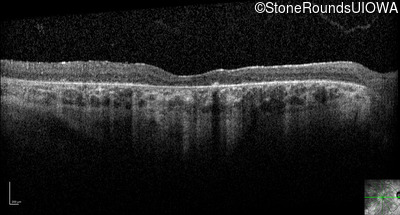

Optical Coherence Tomography - Right - 20/200 +2

Exemplar / OCT Stack